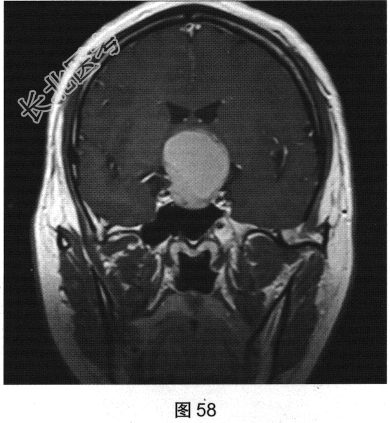

- 多项选择题2.[提示]患者行垂体MRI检查,见图55~图59。患者MRI检查可见哪些阳性影像学表现( )

A、矢状位增强扫描显示垂体及垂体柄显示不清

B、冠状位T1WI上呈等高信号

C、矢状位T1WI上视交叉抬高

D、冠状位T2WI上呈等高信号

E、矢状位T1WI上垂体显示不清

F、冠状位T1WI上可见钙化信号影

G、冠状位增强扫描显示实性部分明显均匀强化

H、MRI示鞍区囊实性占位性病变

I、冠状位增强扫描显示双侧海绵窦受侵